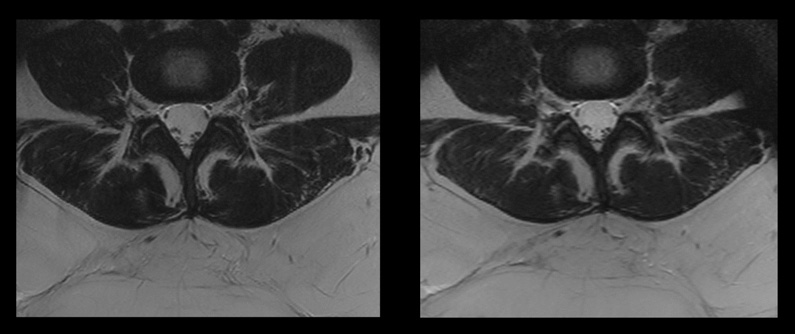

Links: Herkömmlicher Scan mit SAR von 2,5 W/kg und Scandauer 7:33 Minuten

Rechts: Compressed SENSE Scan mit SAR 1,9 W/kg und Scandauer 3:21 Minuten